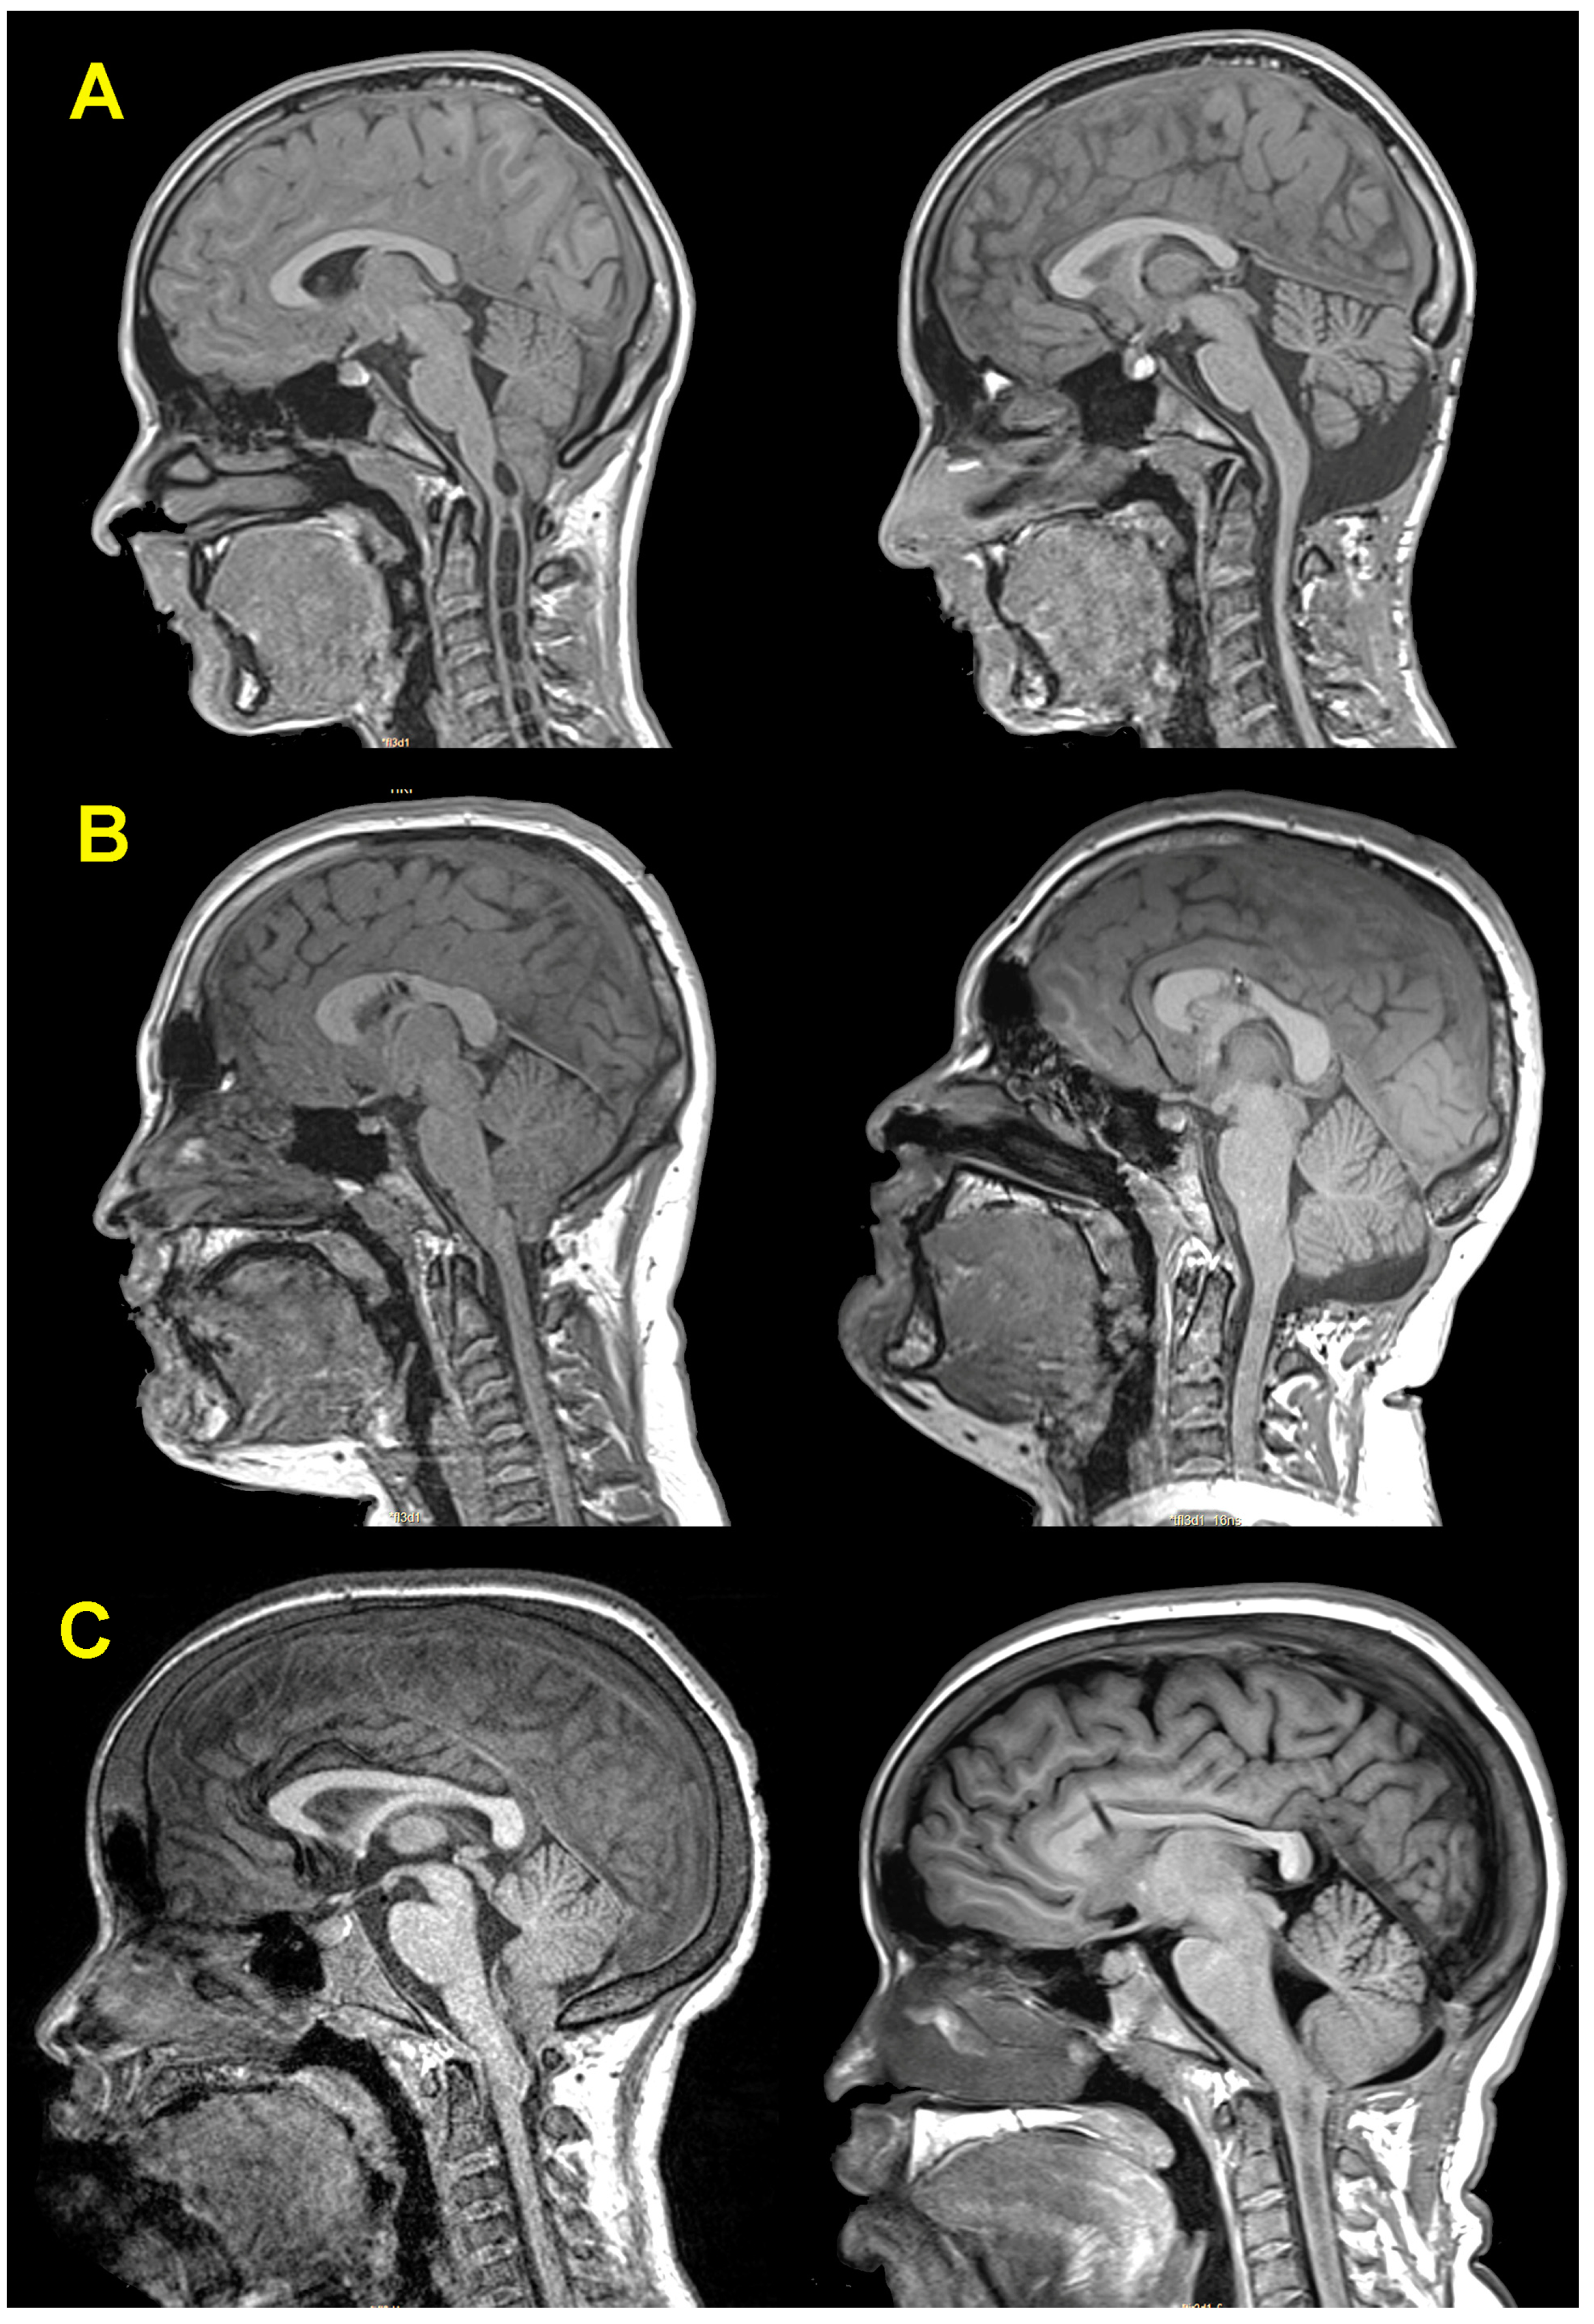

3.5. Neuroimaging Findings before and after Surgery